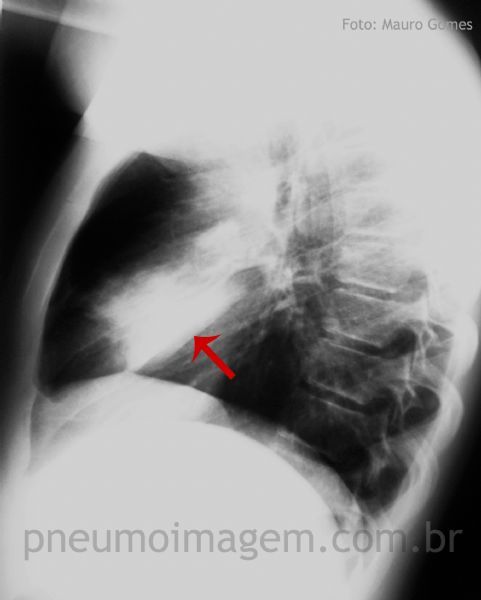

PNEUMONIA EM LOBO MÉDIO

Opacidade em lobo médio. Habitualmente no comprometimento do lobo médio há a perda do contorno da sombra cardíaca à direita, o que ocorre nesta imagem, mas não de um modo tão característico. Seios costofrênicos livres indicam ausência de derrame pleural.

A opacidade em lobo médio pode ser mais bem caracterizada pela incidência em perfil. Observe que a lesão se sobrepõe à sombra cardíaca e está delimitada pela fissura oblíqua (seta). Chaves: cissura oblíqua.

The opacity in the middle lobe may be better characterized by lateral view. The lesion overlaps the cardiac shadow and is delimited by oblique fissure (arrow).